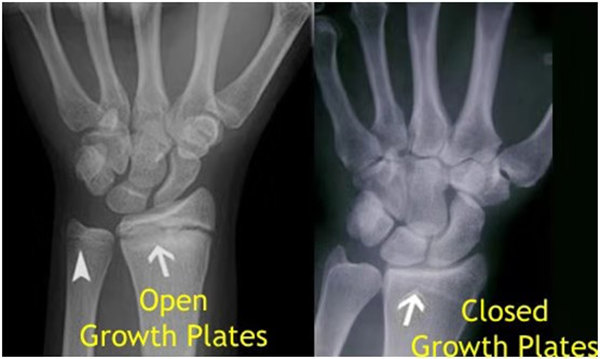

其實想要了解孩子的生長發(fā)育情況或者說孩子未來身高的趨勢,測骨齡是個好辦法。臨床上通常拍攝兒童的左手正位X光片 , 采用《中華-05》骨齡標(biāo)準(zhǔn)對手腕骨發(fā)育程度進行骨齡評價。

我們都知道,人體的高矮是由骨骼的生長發(fā)育決定的,特別是下肢長骨。長骨呈長管狀,在長骨的兩端有一種專管骨骼生長的骺軟骨,它與干骺端之間有一盤狀軟骨結(jié)構(gòu)稱為骺板(線),在幼兒的X光片上表現(xiàn)為一條較寬的透光帶。 (見下圖)

未成年時隨著年齡的增加骺軟骨端不斷骨化,骨骼就不斷增長。當(dāng)骨骺線完全閉合時骨骼就停止生長,個子也就不再增長了。一般骨骺端完全閉合的年齡是18~20歲左右。